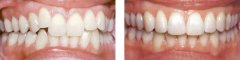

孩子牙齿拥挤可以做隐形矫正吗?

随着生活条件提高,食物越来越精细化,孩子的牙齿就会因为缺乏应有的锻炼,...【详细】